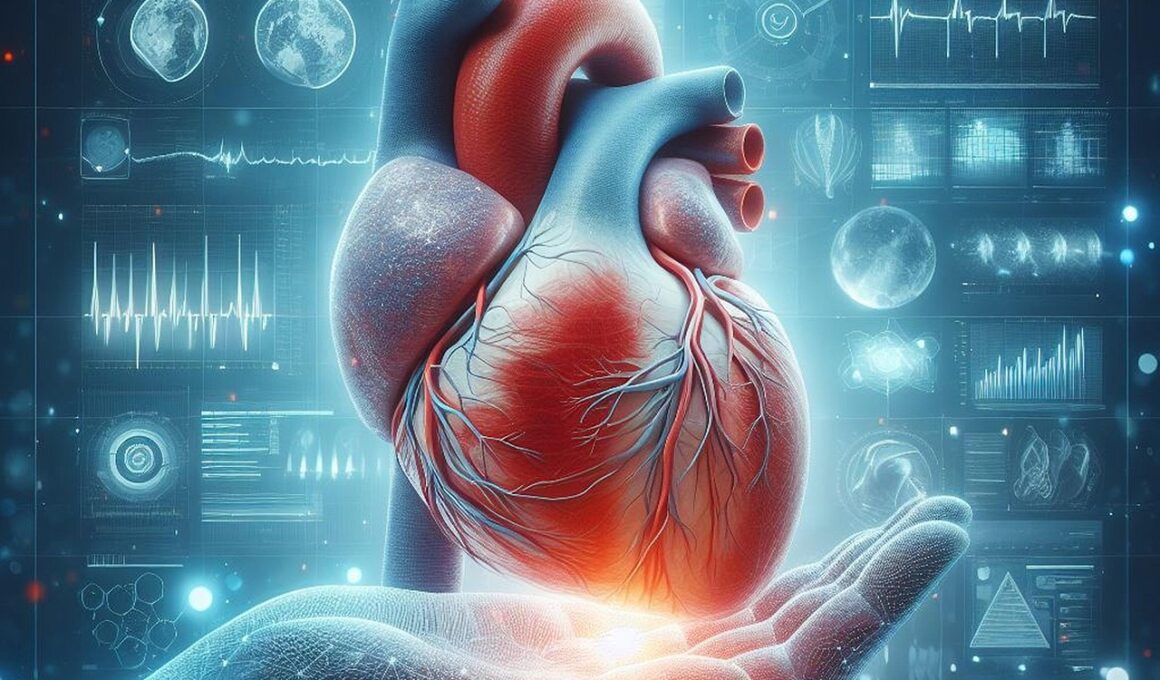

The Impact of Handball on Cardiovascular Health

Handball is an intense team sport that not only provides exhilaration but also significantly benefits cardiovascular health. Engaging in regular handball matches can improve heart function, enhance circulation, and promote overall physical fitness. Studies indicate that players experience increased heart rates, which help in strengthening their cardiac muscles. By participating in this dynamic game, individuals can reduce the risks of cardiovascular diseases, such as heart attacks and hypertension. Handball involves running, jumping, and quick lateral movements that elevate aerobic fitness levels. These aerobic exercises are crucial for maintaining a healthy heart and circulation system. Additionally, consistent practice improves endurance and stamina, higher metabolic rates, which in turn assist in weight management. As players practice their skills, they also improve their coordination and agility. This not only results in a more capable athlete but contributes to a healthier lifestyle. Consequently, handball can be seen as both a competitive sport and a form of physical exercise. Emphasizing teamwork and cooperation, handball fosters social connections while enhancing physical health. Ultimately, the positive impact of handball is significant for participant well-being and cardiovascular fitness.

Taking part in handball activities can lead to remarkable improvements in cardiovascular endurance, providing various health benefits. As players consistently train and compete, they experience a significant boost in heart health, which is essential for athletes at any level. Handball players often undergo rigorous training regimens that include interval training, strength drills, and skill practice. Each session challenges their cardiovascular system, fostering adaptations that promote heart efficiency. This sport demands both stamina and explosive power, translating into higher oxygen uptake during intense plays. Studies show that cardiovascular workouts, as performed during handball, stimulate the heart to pump blood more effectively, thus improving overall circulation. This increased circulation helps to maintain healthy blood pressure levels and reduces the risk of heart diseases. Moreover, playing handball encourages individuals to push their physical limits while staying motivated within a team environment. Emotional well-being is enhanced through social interactions and competitive spirit, further supporting cardiovascular health. Staying committed to consistent practice allows players to sustain their endurance and continuously improve their cardiovascular fitness as athletes. Thus, engaging in handball offers a multifaceted approach to achieving better heart health.